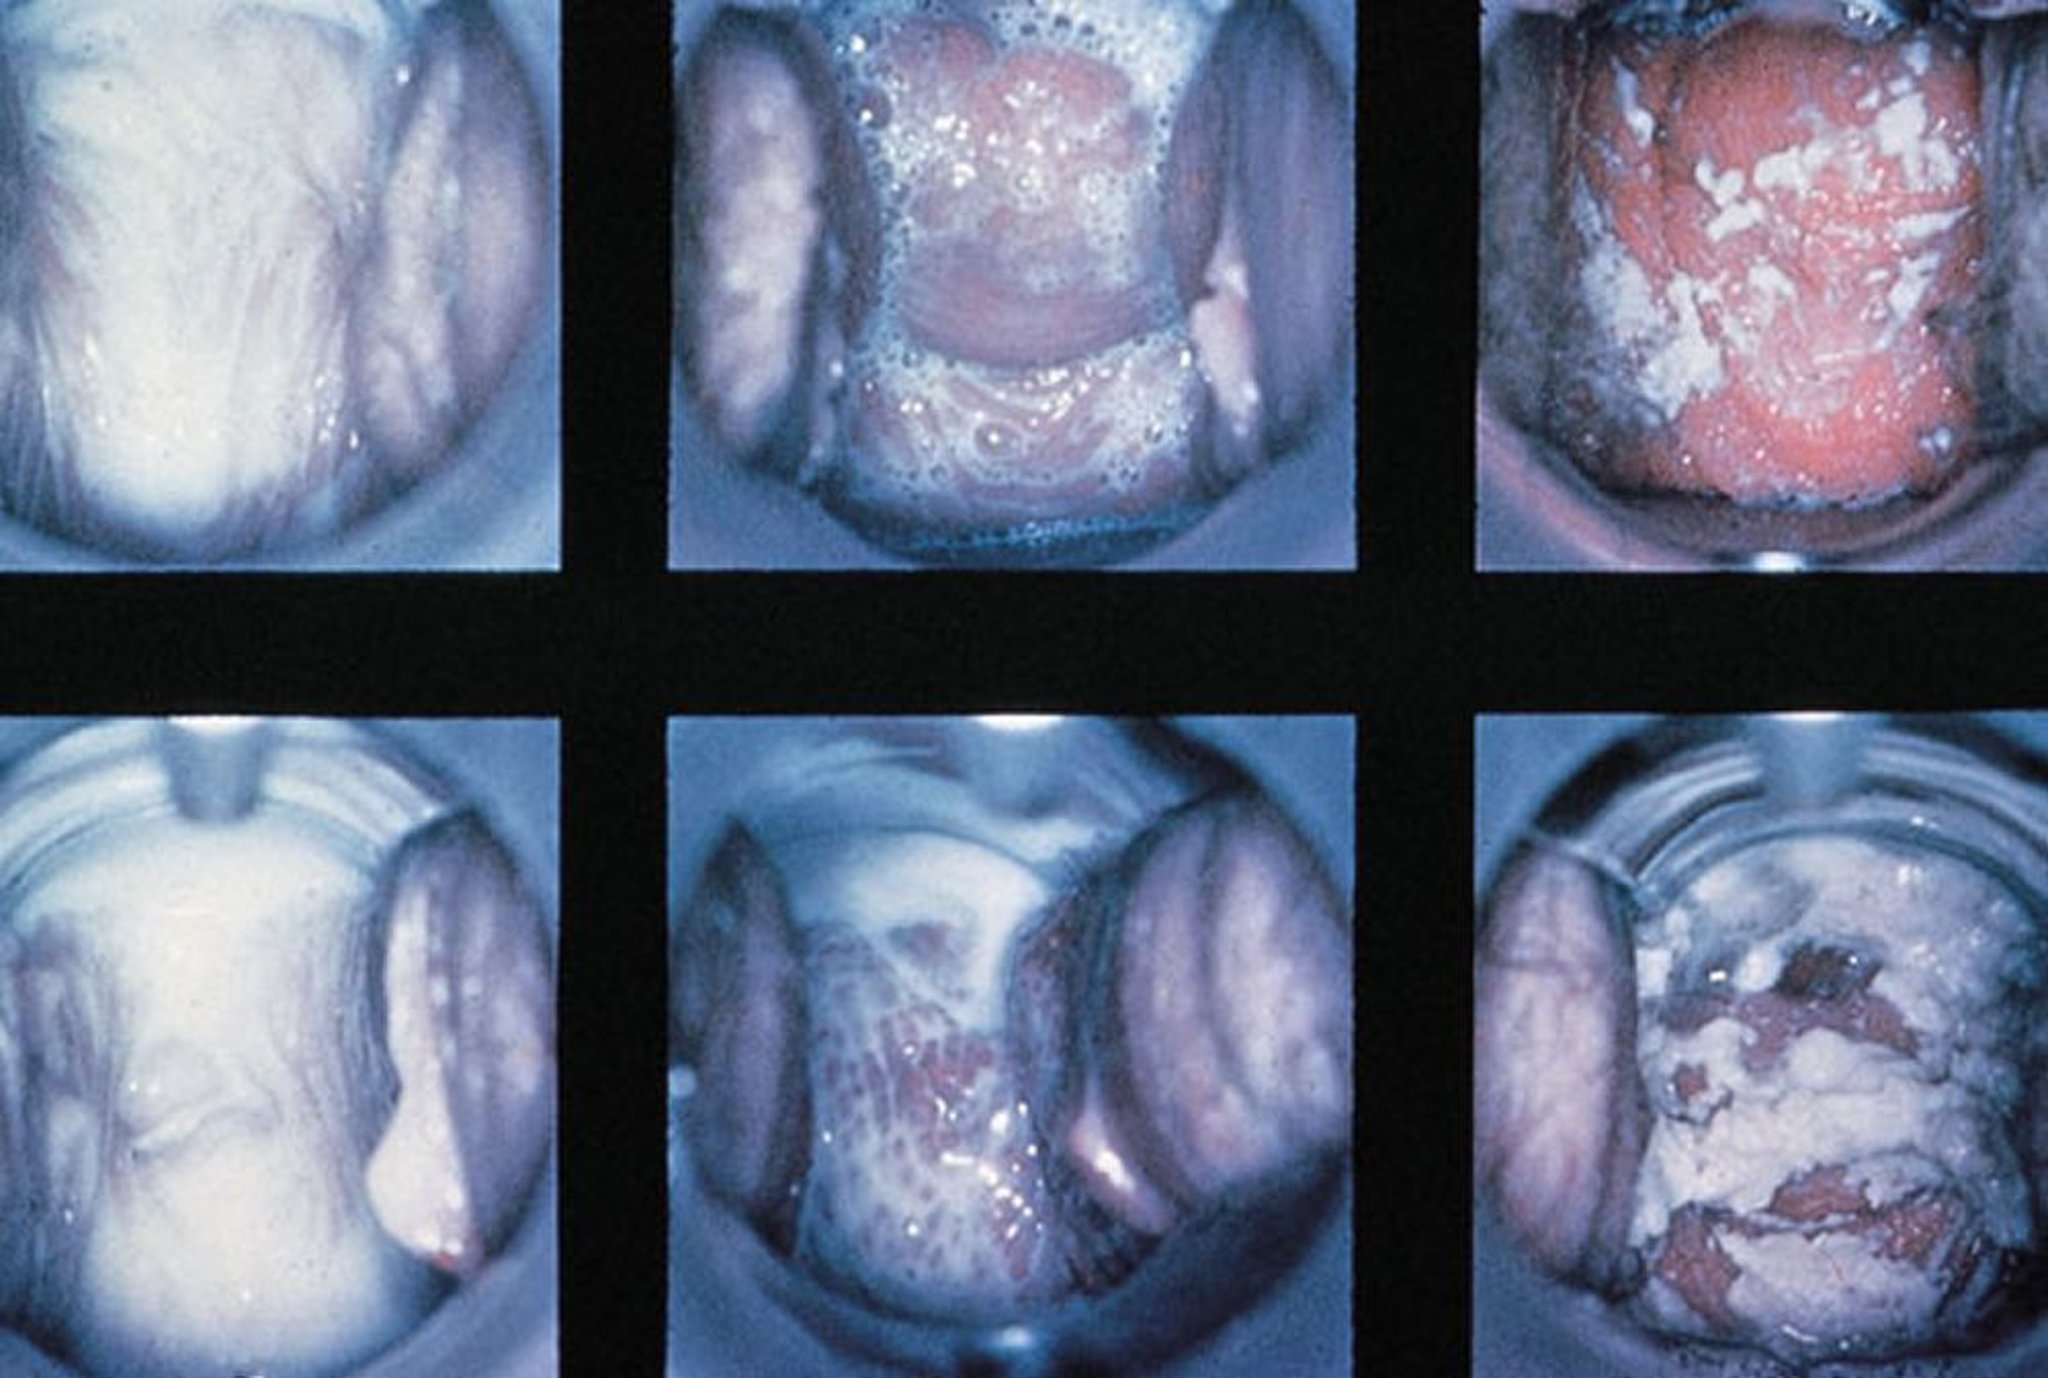

Осмотр в зеркалах при вагините

Отражены показатели в пределах нормы, трихомонадный вагинит с пенистыми выделениями и кандидозный вагинит с густыми, белыми выделениями (слева на право).

By permission of the publisher. From Spitzer M, Mann M. In Atlas of Clinical Gynecology: Gynecologic Pathology. Edited by M Stenchever (series editor) and B Goff. Philadelphia, Current Medicine, 1998. (Courtesy of the International Society for the Study of Vulvar Disease, from the collection of the late Dr. Herman Gardner.)